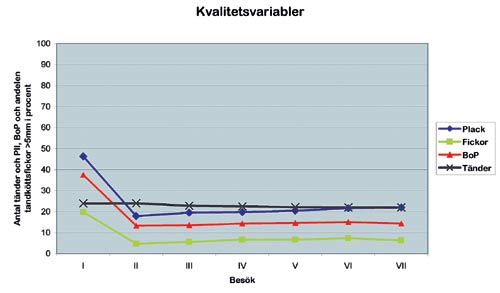

Övertandläkare Göran Söderholm vid specialistkliniken för parodontologi i Malmö konstruerade ett dataprogram för att kvalitetssäkra patientbehandlingen. Följande variabler registrerades vid patientens första besök (Fig. 1.):

Fig. 1. Diagrammet illustrerar kvalitetsvariablerna antalet tänder, plackindex, pli, blödningsindex, bop och andelen tandköttsfickor >5 millimeter vid olika besök. Primärundersökning (I), efter hygienbehandling (II), när den aktiva behandlingen är klar, remissvarsdatum (III), 1 år efter remissvar (IV), 2 år efter remissvar (V), 3 år efter remisssvar (VI) och 4 år efter remissvar (VII).

(I): antalet kvarvarande tänder, andelen fickor > 5 millimeter, plackindex (PLI) enligt Ainamo & Bay (2) och blödningsindex (bleeding on probing (BOP)).

Samma variabler registrerades när den icke-kirurgiska och den kirurgiska behandlingen var slutförd (II), samt när remissvaren skrevs (III).

En grupp patienter med tidigare grava skador fick ingå i ett stödbehandlingsprogram. De undersöktes enligt modellen ovan 1 (IV), 2 (V), 3 (VI) och 4 år efter behandlingen (VII).

I slutet av maj 2003 var antalet registrerade patienter vid kliniken 6 730. Vid det första besöket vid specialistkliniken hade patienterna i medeltal 24 egna tänder. När behandlingen var slutförd hade patienterna förlorat i medeltal 1 tand. Fyra år efter behandlingen hade de förlorat ytterligare 1 tand.

Den låga tandmortaliteten överensstämmer väl med andra långtidsuppföljningar av parodontitbehandlade patienter (3 – 5). De visar att de parodontala problemen går att behandla utan att många tänder måste extraheras. Patientmaterialet visade även att andelen tandköttsfickor > 5 millimeter vid första besöket var cirka 20 procent. Omedelbart efter behandlingen var andelen cirka 5 procent och efter 4 år cirka 6 procent. Inledningsvis var medelvärdena för plack och blödning 46 respektive 38 procent. Efter behandlingen föll motsvarande värden till 18 respektive 13 procent.